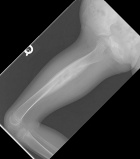

4 year old female with an eight month history of limping and favoring the left lower extremity

Zoom image: Radiological image Radiological image.